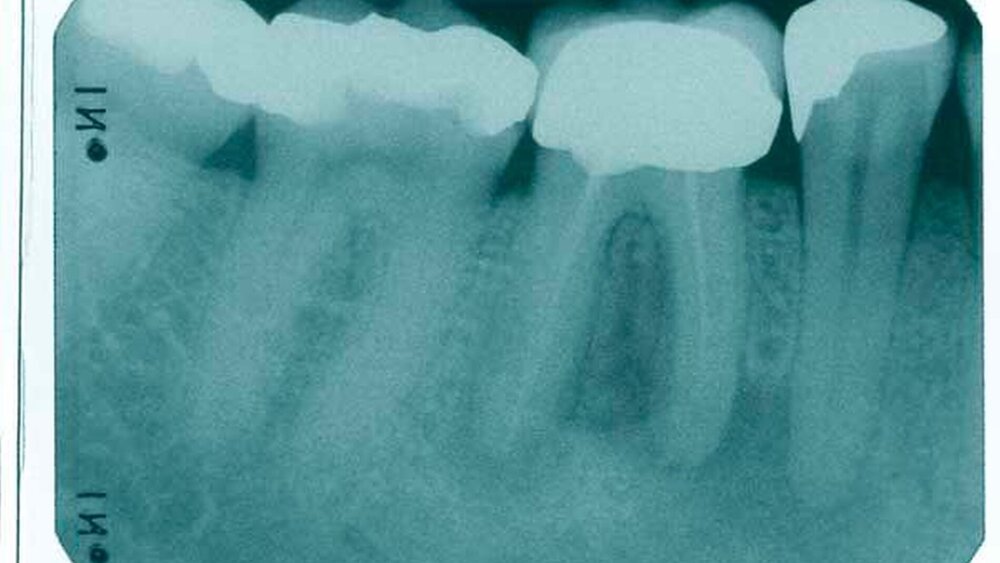

Der Fall: Cäcilia S. ist GKV-versichert. Nach ihrem berufsbedingten Umzug stellt sie sich im neuen Wohnort mit der Notwendigkeit einer Überkronung des Zahnes 24 in der Praxis von Dr. Peter B. vor. Der Befund ergibt ein suffizient konservierend versorgtes Gebiss mit einer Aufbaufüllung am zu überkronenden Zahn, der gemäß Anamnese auch endodontisch versorgt wurde. Ein mitgeführtes, etwa vier Jahre altes Röntgenbild, das vom früheren Zahnarzt der Patientin, Dr. Otto T., unmittelbar nach Abschluss der Wurzelkanalbehandlung angefertigt wurde, zeigt eine an beiden Kanälen bis ins letzte Drittel reichende, also den kassenzahnärztlichen Vorgaben entsprechende Wurzelfüllung.

B. beschließt, eine neue Röntgenaufnahme anzufertigen, auf der jedoch die Wurzelfüllung nur noch schwach erkennbar ist und im oberen Drittel der Kanäle endet. Auf Nachfrage gibt die Patientin an, sie habe für die Durchführung der Wurzelbehandlung nach aktuellem wissenschaftlichem Standard in einer deutschen Großstadt seinerzeit 250 Euro zuzahlen müssen. Zunächst zieht B. einen Mangel im Entwicklungsprozess seiner Röntgenbilder in Erwägung und fertigt unter sorgfältiger Abwägung eine weitere Aufnahme an, die aber den gleichen Befund zeigt. Daraufhin beschließt er, den vorbehandelnden Kollegen telefonisch zu kontaktieren. Der erklärt in diesem Gespräch, dass in seiner Praxis ausschließlich Calciumhydroxid zum Einsatz kommt. B. berichtet von der Resorption des Materials und gibt an, zunächst eine Revision durchzuführen, anschließend den Zahn lege artis abzufüllen und nach Ausheilung die prothetische Versorgung bei der Krankenkasse der Patientin zu beantragen, da nach den gegebenen Umständen eine Ablehnung des Antrags zu erwarten sei. T. antwortet daraufhin, dieses Problem habe er regelmäßig, würde es aber durch erneutes Einbringen von Calciumhydroxid und die zeitnahe Anfertigung eines Röntgenbildes umgehen: Mit der neuen Röntgenaufnahme habe es noch nie Probleme mit Krankenkassen im Zusammenhang mit beantragten prothetischen Versorgungen gegeben.